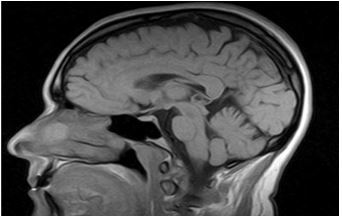

Chụp MRI sọ não: chưa thấy bất thường